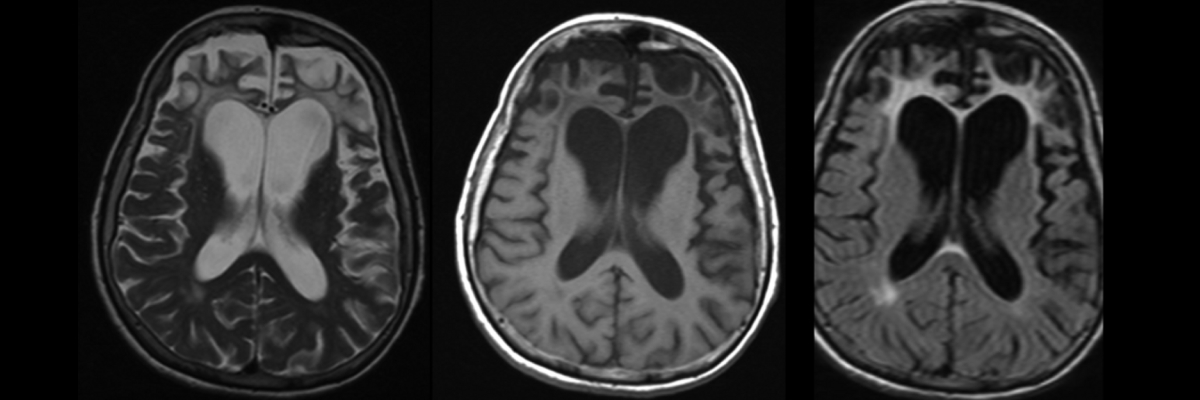

Hastada Pick hastalığına neden olan genin olup olmadığına bakmak için DNA’yı incelemeyi sağlayan bir kan tahlili de yapılabilir. Kan tahlilleri ayrıca bunama belirtilerine neden olan B12 vitamini eksikliği, hipertiroidizm, frengi gibi hastalıkların teşhis edilmesini de sağlar. Bunlara ek olarak beynin detaylı bir şekilde incelenebilmesi için MR, EEG, CT ya da PET gibi görüntüleme yöntemleri gerekebilir. Bunlar sayesinde beyinde meydana gelen değişiklikler ve beynin şekli rahatlıkla görülür. Aynı zamanda görüntüleme yöntemleri ile beyin tümörleri ya da bunama semptomlarına yol açan diğer tıbbi durumlar da ekarte edilmiş olur.